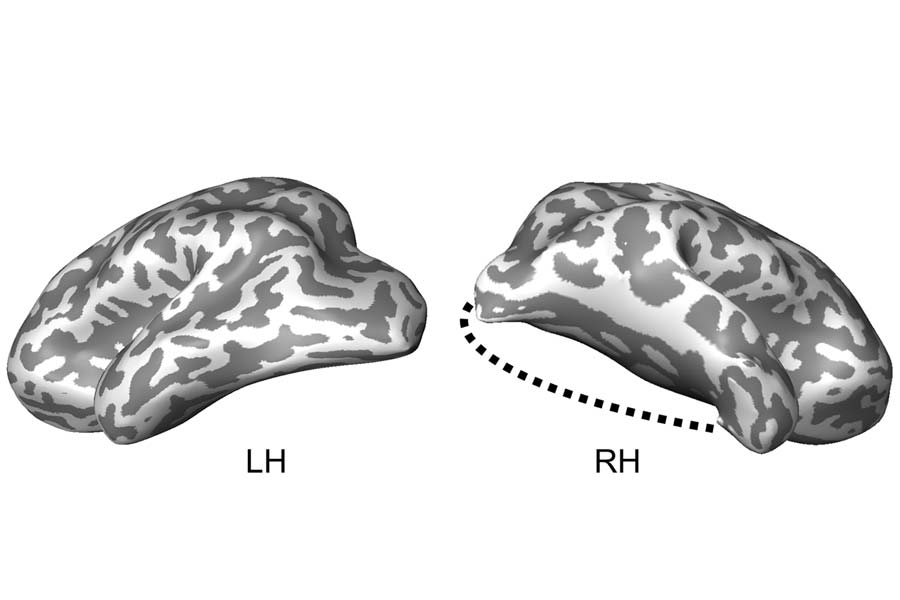

.Carnegie Mellon University and University of Pittsburgh have received a $3.8M nimh grant to diagnose suicidal thinking using brain imaging. Findings could improve how clinicians detect and treat suicidal patients: cmu.edu/dietrich/news/…